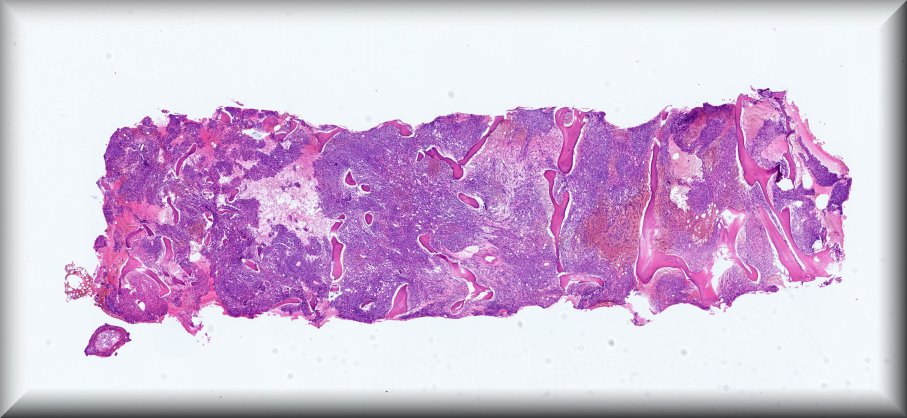

Caso 11.- Tania Cambero González, Carolina Martínez Ciarpaglini, Antonio Ferrández Izquierdo.

Hospital Clínico Universitario de Valencia.

Mujer de 80 años con clínica de astenia e hiporexia de dos meses de evolución, pérdida de 6 kg de peso y esplenomegalia a la palpación, que presenta reacción leucoeritroblástica en frotis de sangre periférica, así como bicitopenia severa a expensas de anemia y trombopenia. Se solicita biopsia de médula ósea para descartar infiltración.